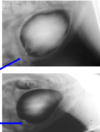

what is this?

Dilation of renal pelvis

Chunky ureters

What is going on?

Hydronephrosis/ dilated ureters